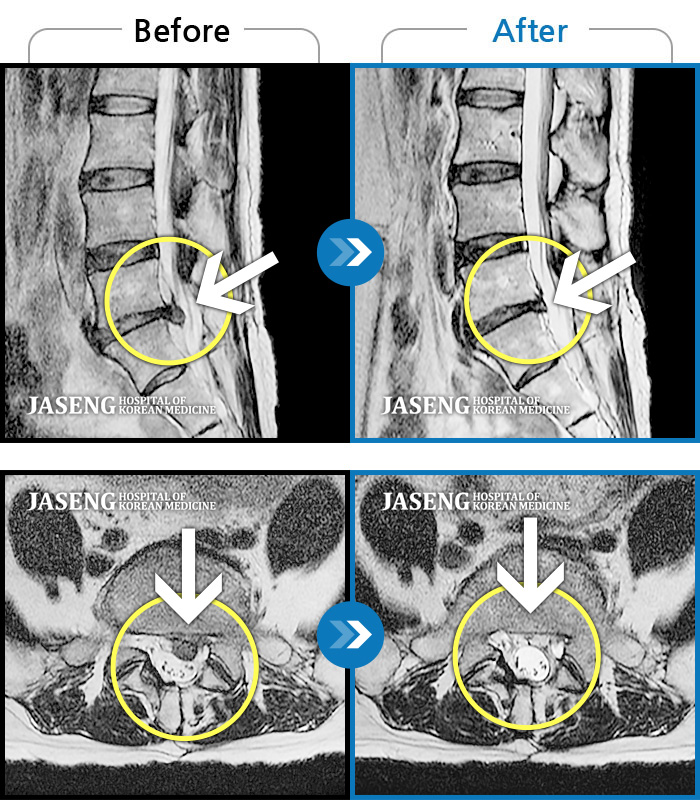

허리디스크

인천 · 강아현 원장

처음 내원시 우측 골반 및 종아리 통증으로 걷기 및 허리 굴신이 어려운 상태였습니다

촬영시기

2019.04.18 ~ 2023.12.12

2023.12.15